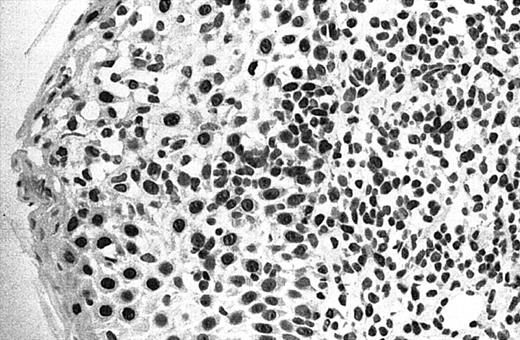

Illustration of IHC staining of JUNB in an SS patient (case 8).

This photograph (original magnification × 40) revealed strong nuclear expression of JUNB by large epidermotropic tumor cells with absent expression in small dermal mononuclear cells. Epidermal basal keratinocytes also expressed JUNB, representing a useful internal control.

Of 69 PCLs analyzed by IHC, 44 cases showed nuclear JUNB expression in a proportion of tumor cells (64%) (Table 2). This included 21 (91%) of 23 SS, 6 (75%) of 8 C-ALCL, 5 (50%) of 10 MF, 9 (43%) of 21 PCBCL, 2 (50%) of 4 NK cell lymphoma, and 1 (50%) of 2 systemic FL (Table 2). Seven cases (10%) revealed expression of JUNB by all tumor cells (+++) (overexpression), including 5 C-ALCL (63%) and 2 SS cases (9%) (Table 2; Figures2-3). Epidermal basal and suprabasal keratinocytes also expressed JUNB, which represented a useful internal control to indicate the efficiency of immunohistochemistry (Figure 2). All the positively stained PCBCL cases showed only occasional cells expressing JUNB (+) (Table 2), and in this case it is difficult to conclusively establish whether expression is restricted to tumor cells or activated B cells on morphology.